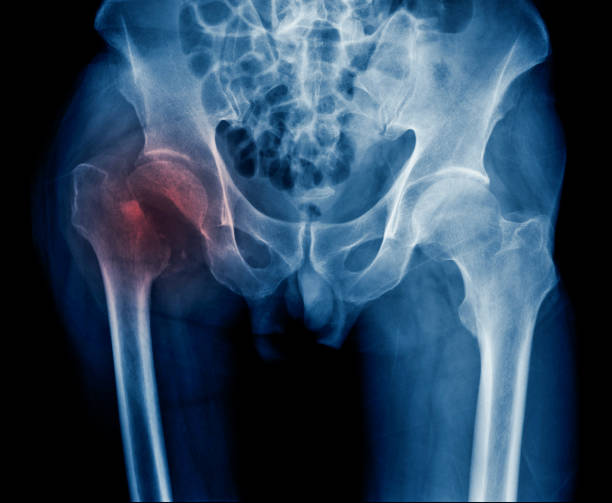

고관절 충돌 증후군

고관절 충돌 증후군은 엉덩이 통증의 주요한 원인 중 하나입니다. 이 질환은 골반 뼈와 대퇴골 사이에서 발생하는 충돌에 의해 2 관절 사이의 연골이 손상되는 질환입니다. 고관절의 구조적인 문제나 잘못된 자세, 과도한 스트레칭 등으로 발생할 수 있습니다.